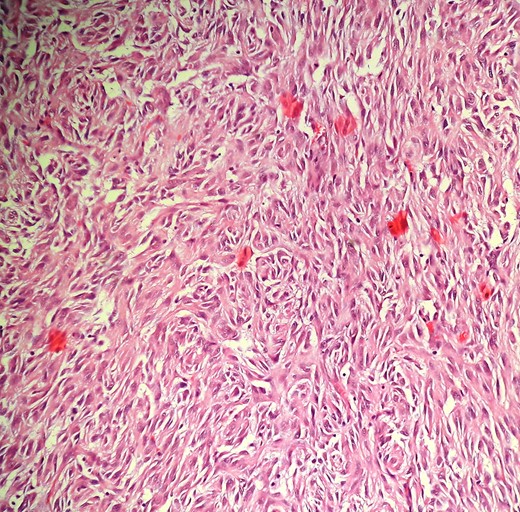

Intraoperatively, to our surprise, a tumor was arising from the mesentery of the second loop of jejunum. The entire mass was present in the right upper quadrant. It was six in number, multicentric, solid, bosselated and adhered to the serosal aspect of the jejunum. Furthermore, the omentum was wrapped around the tumor, which was in fact due to the necrotic changes in one of the tumor, with impending perforation. The tumor was excised enbloc with the jejunum with macroscopically clear margin and primarily anastomosed. Cut section showed whitish-solid tumor with whorled appearances, with one tumor with necrotic changes showing tumor enteric fistula (Fig. 2). Postoperative period was straightforward and was discharged on Day 5. Pathological examination of the specimen revealed gastrointestinal stromal tumor (GIST) of the jejunal mesentery (mitotic figure—13/50 HPF, areas of necrosis suggesting high grade), which on immunohistochemistry stained strongly for CD117 and CD34 (Fig. 3). One of the dissected lymph node in the mesentery showed tumor deposits. The patient had been on imatinib 400 mg once daily for the last 6 months, and unfortunately had liver recurrence on follow-up CT scanning.

Photomicrograph (H&E,×100) showing proliferation of spindle to epitheloid tumor cells in sheets and nests.